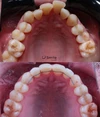

Diş Çapraşıklığı